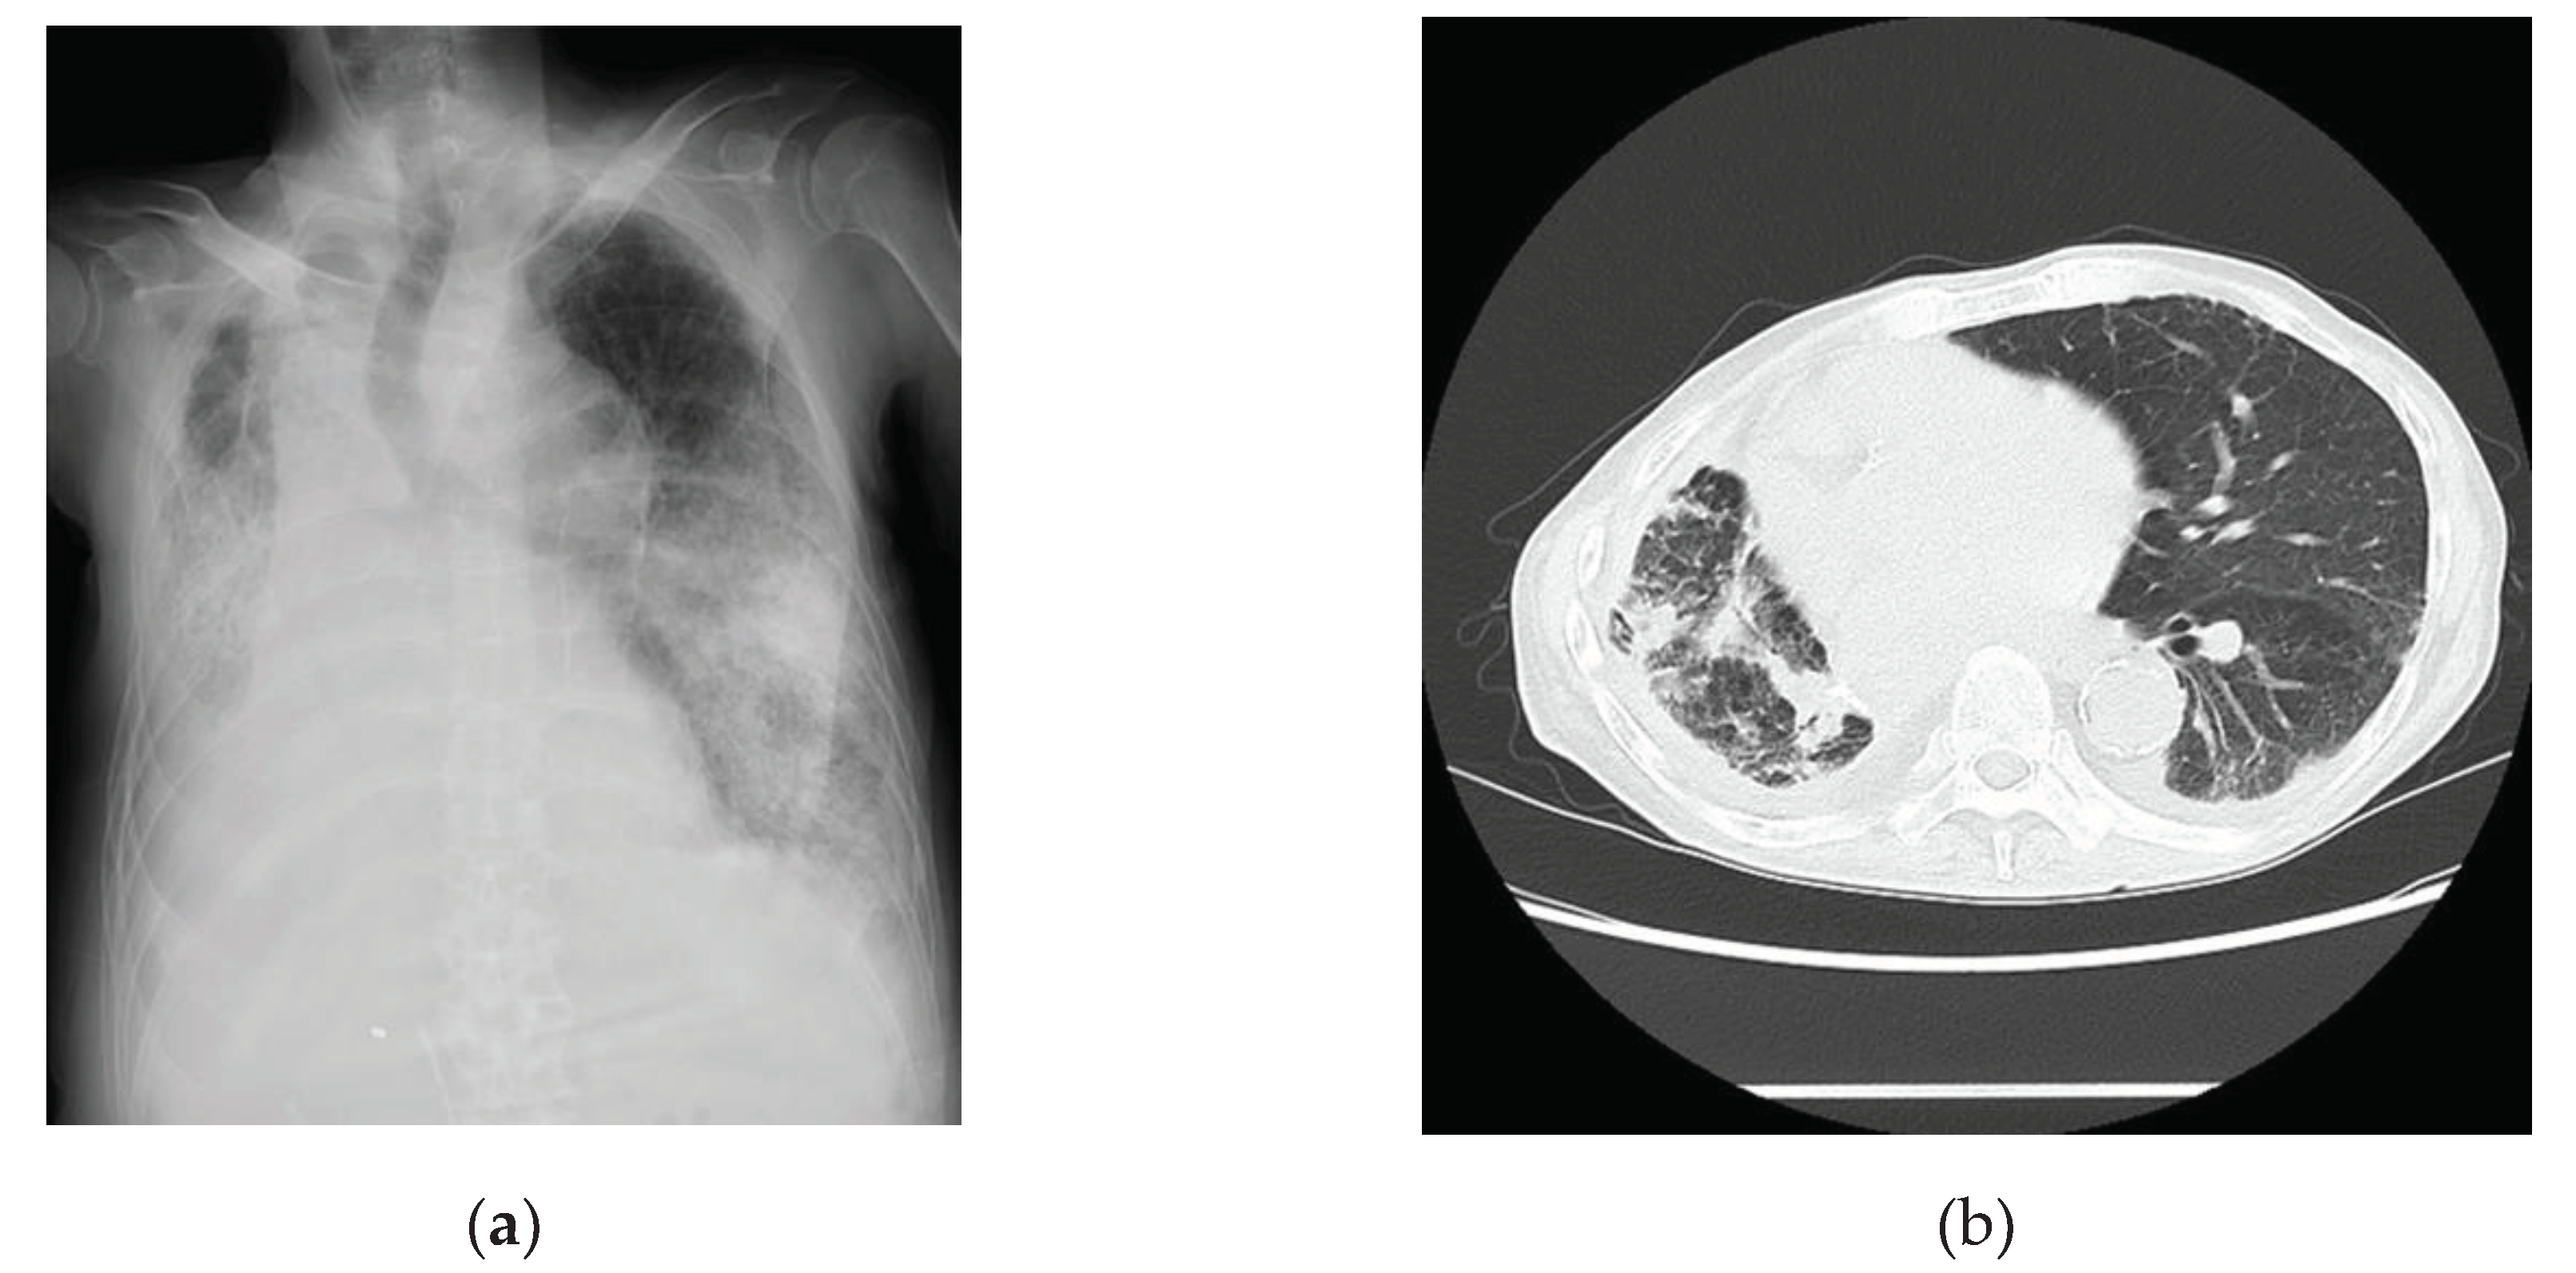

2.3. Case 3